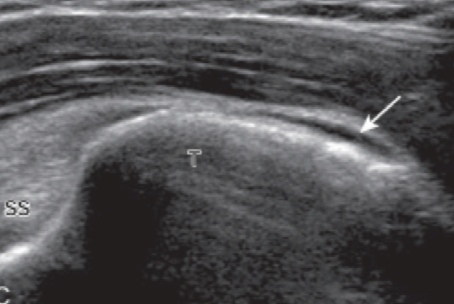

목차 반응형어깨 검사를 위하여 환자는 의자의 발이 고정된 등받이 없는 회전의자에 앉고, 검사자는 이동성이 좋은 바퀴 달린 의자에 앉는다. 환자의 왼쪽어깨를 검사할 때에는, 환자가 초음파기기를 향하여 앉고, 검사자는 초음파기기와 환자사이에 엇비슷하게 앉는다. 오른쪽 어깨를 검사할 때에는, 검사자가 기계를 향하여 앉고, 환자는 검사자를 엇비슷하게 마주 보고 앉는다. 어깨의 초음파 검사는 적어도 10 Mhz 이상의 주파수를 가진 탐촉자를 사용한다. 환자의 체격이 좋고 비대하거나, 어깨뼈오목테두리(glenoid labrum)등, 어깨 깊은 곳에 있는 구조물을 보려면 낮은 주파수의 탐촉자를 쓰기도 한다. 검사 항목을 빠뜨리지 않고 검사를 하기 위하여, 다음에서 설명하는 검사 순서에 따라 단계별로 하는 것이 중요하다. 다른 관절에서는 필요한 부분만 골라서 중점적으로 검사하기도 하지만, 어깨에서는 통증의 원인이 애매하고, 또 다른 부위의 병변에 의한 통증이 어깨에 연관통증(referred pain)을 나타낼 수 있고, 또 어깨의 질병이 다른 부위에 연관통증을 일으킬 수 있기 때문이다. 물론, 통증이나 증상이 있는 곳을 추가로 검사하는 것은 필수적이다. 자세 1. 두 갈래 근 긴 힘줄환자는 검사받는 팔의 손바닥이 위를 향하게 하여 손등을 환자의 넙다리에 놓는다. 이 자세를 중립 상태라고 한다. 탐촉자를 가로축 방향으로 어깨의 앞쪽에 놓으면 두 갈래 근 긴 힘줄(long head of biceps brachii tendon)이 두 갈래 근고랑에 놓인 것을 볼 수 있다.  두갈래근 긴힘줄 초음파 영상(short axis) 이 자세는 어깨의 앞쪽에서 중요한 표식자(landmark)인 두 갈래 근고랑의 움직임을 보면서 회전근띠를 검사하기에 좋다. 탐촉자를 피부에 대면 두갈래근 긴 힘줄이 정상인데도 검고 낮은 에코로 보인다. 이를 비등방성(anisotropy) 허상이라 한다. 그 이유는 힘줄이 아래로 갈수록 비스듬하게 기울기를 가지면서 깊어지기 때문이다. 탐촉자를 힘줄에 대해 90도가 되도록 조절하면 비등방성이 사라지고 힘줄은 높은 에코로 바뀐다. 가로축 방향에서 위, 아래로 두 갈래 근 긴 힘줄을 따라가면서 검사한 뒤에 탐촉자를 90도로 돌려서 세로축 방향에서 검사한다. 마찬가지로 입사 초음파가 힘줄에 대해 직각이 되도록 탐촉자의 각도를 조절하면서 검사한다. 세로축 방향에서 작은 거 친면은 특징적으로 세모꼴로 보이는데 그 바로 바깥쪽의 두 갈래 근고랑에는 두 갈래 근 긴 힘줄이 세로로 길게 놓여있다.  두갈래근 긴힘줄 초음파 영상(longitudinal) 자세 2. 어깨밑근과 두갈래근 긴 힘줄의 탈구자세 1 '중립자세'에서 탐촉자를 어깨 앞쪽에 가로축 방향으로 놓으면 두 갈래 근 긴 힘줄(biceps tendon)보다 안쪽으로 어깨밑 근(subscapularis)이 보이는데, 어깨밑근의 긴 축영상(long-axis images)이다. 이 자세에서 어깨밑근은 심한 비등방성 때문에 매우 검게 보인다. 환자의 팔을 바깥돌림(external rotation)하면 어깨밑근이 입사 초음파에 대해 수직으로 놓이게 되면서 비등방성이 사라지게 되고 정상적인 높은 에코로 바뀐다. 이 자세에서 탐촉자를 위, 아래로 움직여서 어깨밑근이 작은 거 친면에 넓게 붙는 것을 본다. 팔을 안-바깥돌림(internal and external rotation)하면서 두갈래근 긴 힘줄이 두 갈래 근고랑에서 벗어나지 않음을 관찰한다. 두 갈래 근 긴 힘줄의 부분이탈이나 어긋남(subluxation or dislocation)이 팔의 바깥돌림에서만 나타날 수 있다. 탐촉자를 90도 돌려 세로로 놓으면, 탐촉자는 어깨밑근의 주행방향에 대해 90도 각도로 놓이게 되고, 어깨밑근을 짧은 축영상(short-axis images)에서 검사한다. 어깨밑근의 짧은 축영상에서, 높은 에코의 힘줄다발(tendon bundle) 사이사이에 낮은 에코의 근육이 줄무늬(striation)로 보이는데 이는 정상소견이며, 공간복합기능(spatial compound function)이 없는 초음파기기에서는 대조도가 더 뚜렷하게 보인다. 자세 3. 봉우리빗장관절 및 봉우리밑-세 모근밑 윤활주머니봉우리빗장관절(acromioclavicular joint)은 탐촉자를 빗장뼈(clavicle) 먼쪽(distal)에 빗관상면(coronal-oblique plane)으로 놓고 손으로 만지면서 그 위치를 찾거나, '자세 1' 에서처럼 가로축 방향으로 놓은 탐촉자를 그대로 어깨 위로 옮기면서 찾아간다. 관절을 이루는 두 뼈는 높은 에코로 보이고, 관절강(joint cavity)은 낮은 에코로 나타난다. 탐촉자를 관절 위에 놓은 상태에서, 탐촉자를 잡지 않은 검사자의 반대 손(free hand)으로 환자의 팔(검사받는 쪽)을 잡고 당기면서 검사하면, 관절의 이완(laxity)을 알 수 있다. 다른 방법은 환자의 손(검사받는 쪽)을 반대편 어깨 위로 올려서 앞뒤로 움직여보면 관절강이 넓어지는 것을 알 수 있다. 탐촉자를 바깥쪽으로 좀 더 옮기면 깊은 부위에 위팔뼈(humerus)의 큰 거 친면이 보이는데, 이때 봉우리밑 -세 모근밑 윤활주머니(subacromial -subdeltoid bursa)의 아래쪽(dependent portion)에 고인 액체를 관찰할 수 있다.  subacromial -subdeltoid bursa 자세 4. 가시아래근, 작은 원근, 뒤쪽어깨뼈 오목테두리환자가 의자에 앉은 채로 180도 돌면, 검사자는 환자의 어깨 뒤쪽을 보면서 검사하게 된다. 처음에는 환자의 손바닥을 위로 가게 한 중립상태에서 검사한다. 탐촉자를 어깨 뒤에서 위팔뼈머리(humeral head) 위치에서 가로축 방향으로 놓은 다음 가시아래근(infraspinatus)의 주행을 따라 탐촉자의 바깥쪽 끝을 약간 위로 비스듬하게 기울이면, 가시아래근의 힘줄이 근육의 가운데에서 나와서 위팔뼈머리에 붙는 곳을 볼 수 있는데, 이 영상은 가시아래근의 긴 축영상이다. 탐촉자를 아래로 약간 옮기면 작은 원근(teres minor)이 보이는데, 가시아래근 힘줄은 근육의 가운데에 있는데 반해, 작은원근 힘줄은 근육에 대해 표재성으로 있다. 탐촉자를 90도 돌려서 세로축 방향으로 놓으면 가시아래근과 작은 원근의 짧은 축 영상이 얻어지는데, 어깨뼈몸 쪽(proximal scapula)에서 근육-힘줄이음부가 보이고, 이곳에서 가시아래근의 크기는 작은 원근의 2배 정도이다. 탐촉자를 바깥쪽으로 비스듬히 옮기면, 근육은 점차 얇아지고, 힘줄이 큰 거 친면에 붙는 것을 볼 수 있다. 다른 방법으로는 어깨뼈가시(scapular spine)를 손으로 만져서 확인한 다음, 탐촉자를 세로로 spine에 놓고 아래쪽으로 옮기는데, 가시 바로 아래 놓인 것이 가시아래근이다. 탐촉자를 가시아래근의 주행을 따라 기울인 긴축 방향으로 놓으면, 근육 깊숙이 어깨관절의 뒤쪽을 볼 수 있는데, 뒤쪽 어깨뼈오목(glenoid)의 끝에 붙은 어깨뼈오목테두리(glenoid labrum)가 세모꼴의 높은 에코로 보인다. 팔을 안 돌림-바깥돌림하는 과정에 동적검사를 하면, 가시아래근 힘줄과 뒤테두리(posterior labrum)를 더 잘 볼 수 있다. 이 위치에서 동적검사를 하면 뒤관절오목(posterior glenohumeral joint recess)에 고인 액체를 볼 수 있고, 또 테두리 째짐(labral tear)을 찾을 수도 있다. 탐촉자를 보다 안쪽으로 약간 옮겨서 가시관절 오목패임(spino-glenoid notch)을 관찰하는 것이 중요하다. 이곳에 테두리 곁낭종(paralabral cyst)이 생기면 볼 수 있다. 팔을 바깥돌림하면 어깨위정맥(suprascapular vein)이 굵어져서 테두리 곁낭종과 비슷하게 보이므로 주의한다. 자세 5. 가시위근가시위근힘줄의 초음파 검사에서 가장 중요한 열쇠는 가시위근(supraspinatus)의 해부학을 이해하고 팔의 위치에 따른 힘줄의 변화를 아는 것이다. 팔을 중립상태로 놓은 자세에서 가시위근힘줄의 긴축영상을 얻기 위해서는 탐촉자를 거친 면위에 관상면을 따라 위치시켜야 한다. 그런데, 이곳에서 가시위근힘줄의 많은 부분은 봉우리뼈 아래에 숨어 있기 때문에 잘 볼 수 없다. 이때 환자의 팔을 안쪽돌림하고, 구부린팔꿉을 몸에 붙인 채로 환자의 손을 환자의 허리 뒤로 옮겨서 바지의 반대편 뒤호주머니에 닿게 하면, 봉우리뼈 밑에 가려진 힘줄이 뼈 밖으로 나타난다. 이자세를 크라스 자세(crass position)라고 한다. 이 자세에서는 위팔뼈머리의 큰 거 친면이 어깨의 앞쪽에 있으므로 탐촉자를 거친 면 위에 세로로 놓으면 가시위근힘줄을 긴축방향에서 검사할 수 있다. 정상 가시위근힘줄은 높은 에코의 섬유다발로 보이고, 위쪽 가장자리가 둥글고 볼록하게 보인다. 관절면 가까이에서 큰 거 친면의 힘줄 붙는 곳에서 힘줄은 아래로 둥글게 구부려지면서(curved downward) 주행하기 때문에 탐촉자의 위치도 그에 따라 각도를 조절하면서 움직여야 하며, 이때 비등방성에 의한 힘줄의 낮은 에코를 병적 소견으로 오인하면 안 된다.  supraspinatus tendon anisotropy 가시위근힘줄이 큰 거 친면에 부착하는 길이는 약 2.25cm 이므로 힘줄의 주행을 따라 탐촉자를 앞뒤로 움직이면서 관찰해야 가시위근힘줄 전체를 검사하는 것이 된다. 또 거 친면의 가장 앞쪽으로 탐촉자를 이동하면서 관절 안 두갈래근 긴 힘줄이 보일 때까지 검사하는 것이 매우 중요하다. 그래야만 가시위근힘줄이 가장 잘 손상되는 앞쪽 끝을 검사할 수 있기 때문이다. 탐촉자를 거 친면의 뒤로 이동함에 따라 위팔뼈머리의 관절면과 거 친면이 만나는 각도가 편평해지고 가시위근힘줄이 깍지 낀 손가락처럼(interdigitating) 보이면서 낮은 에코로 나타나는데, 이는 비등방성 때문이며, 이곳이 가시위근힘줄과 가시아래근힘줄이 만나는 부위이다. 가시위근힘줄을 긴축 방향에서 검사한 다음에 탐촉자를 90도 돌려서 가시위근힘줄을 짧은 축 방향에서 검사한다. 관절 안에서 위팔뼈머리가 볼록하게 높은 에코의 줄(line)로 보이고, 그 바로 바깥을 덮고 있는 관절연골은 낮은 에코로 보인다. 회전근 띠는 아주 가지런한 두께를 보이며, 마치 자동차 바퀴와 비슷하다. 이런 모양으로 보이면 가시위근힘줄을 진짜 축방향에서 제대로 검사함을 의미한다. 가시위근힘줄을 따라 긴축방향으로 탐촉자를 힘줄의 먼 쪽으로 이동한다. 관절연골이 시야에서 사라지면서, 위팔뼈머리의 거 친면이 나타난다. 이 지점에서 힘줄은 점차 가늘어지고 관절밖으로 나오게 된다. 거 친면에서 앞뒤로 3개의 힘줄부착단면(superior, middle and inferior facets)이 있는데 모양이 편평하다. 가시위근힘줄은 위쪽단면전체와 중간단면의 위 1/2에 붙는다. 가시아래근힘줄은 가시위근힘줄과 서로 섞이면서 중간단면에 붙는다. 작은 원근은 아래단면에 붙는다. 탐촉자를 더 먼 쪽으로 이동하면 거 친면이 약간 각진 모양으로 변하고, 힘줄은 점차 얇아지면서 없어진다. 비슷한 방법으로 두 갈래 근 긴 힘줄의 관절 안 부분을 관찰하면서 가시위근힘줄의 가장 앞쪽 끝을 살펴본다. 이 부위가 가시위근힘줄의 손상이 가장 많은 곳이기 때문이다. 두 갈래 근 긴 힘줄과 회전근 간격(rotator interval)은 팔을 바깥돌림한 상태에서 가장 잘 보이는데, 환자의 손바닥을 검사하는 팔 쪽의 엉덩이에 비스듬히 놓는다. 이때 거 친면은 팔을 중립상태로 했을 때와 크라스자세(crass position)를 했을 때의 중간쯤에 위치한다. 따라서 탐촉자도 반쯤 기울어진 각도로 놓는데, 이때 탐촉자가 놓인 축은 위팔뼈와 평행하게 된다.  modified crass position 탐촉자를 90도 돌려서 가시위근힘줄과 회전근간격의 앞쪽을 검사한다. Crass 자세에 비해 변형 Crass 자세는 가시위근힘줄의 앞쪽 끝을 검사하는데 가장 중요한 표식자인 두 갈래 근 긴 힘줄을 보여주는 장점이 있고, 어깨통증이 심한 환자에서 검사하기에 편리하다. 그러나 회전근띠의 크기는 크라스자세에서 긴축 방향 영상에서 측정하는 것이 더 정확할 수 있다. 거 친면의 뒤쪽에서 가시위근힘줄과 가시아래근힘줄이 만나는 부위가 가운데단면이며, 이 부위에서는 회전근띠가 약간 얇게 보일 수 있다. 자세 6. 회전근띠 부딪힘 및 유착성관절염에서 동적검사탐촉자를 어깨 위에 빗관상면으로 놓고, 큰거친면과 봉우리가 모니터에 보이도록 한다. 환자는 힘을 빼고 팔을 몸 가까이에 늘어뜨려서 손이 엎침(pronation) 상태가 되게 한다. 팔꿈치를 구부린 상태에서 환자 스스로 앞-바깥쪽으로 팔을 들어 올리게 하거나 어깨가 아플 때까지 팔을 들어 올려 보라고 환자에게 주문한다. 이렇게 팔을 움직이는 동안에 가시위근이 봉우리 아래로 부드럽게 잘 들어가고 나오는지를 관찰한다. 만약 그렇지 못하면 유착성 관절 막요(adhesive capsulitis)을 시사한다. 봉우리밑-세 모근밑 윤할주머니의 액체가 봉우리 끝에서 고이게 되면 부딪힘(impingement)을 시사하는 소견이다. 반응형